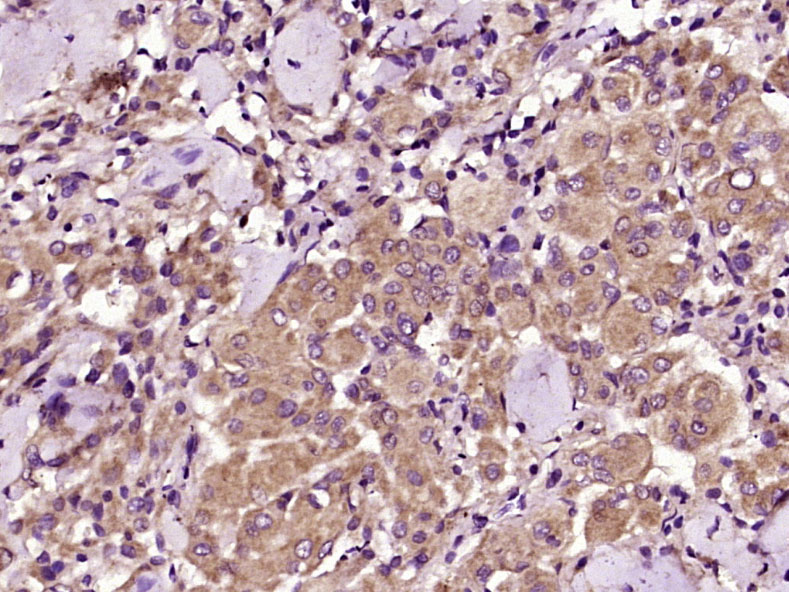

Paraformaldehyde-fixed, paraffin embedded (Mouse adrenal gland); Antigen retrieval by boiling in sodium citrate buffer (pH6.0) for 15min; Block endogenous peroxidase by 3% hydrogen peroxide for 20 minutes; Blocking buffer (normal goat serum) at 37°C for 30min; Antibody incubation with (IGF2R/M6PR) Polyclonal Antibody, Unconjugated (bs-6670R) at 1:200 overnight at 4°C, followed by operating according to SP Kit(Rabbit) (sp-0023) instructionsand DAB staining.

Paraformaldehyde-fixed, paraffin embedded (human liver); Antigen retrieval by boiling in sodium citrate buffer (pH6.0) for 15min; Block endogenous peroxidase by 3% hydrogen peroxide for 20 minutes; Blocking buffer (normal goat serum) at 37°C for 30min; Antibody incubation with (IGF2R/M6PR) Polyclonal Antibody, Unconjugated (bs-6670R) at 1:200 overnight at 4°C, followed by operating according to SP Kit(Rabbit) (sp-0023) instructionsand DAB staining.

Paraformaldehyde-fixed, paraffin embedded (human meningioma); Antigen retrieval by boiling in sodium citrate buffer (pH6.0) for 15min; Block endogenous peroxidase by 3% hydrogen peroxide for 20 minutes; Blocking buffer (normal goat serum) at 37°C for 30min; Antibody incubation with (IGF2R) Polyclonal Antibody, Unconjugated (bs-6670R) at 1:400 overnight at 4°C, followed by operating according to SP Kit(Rabbit) (sp-0023) instructionsand DAB staining.